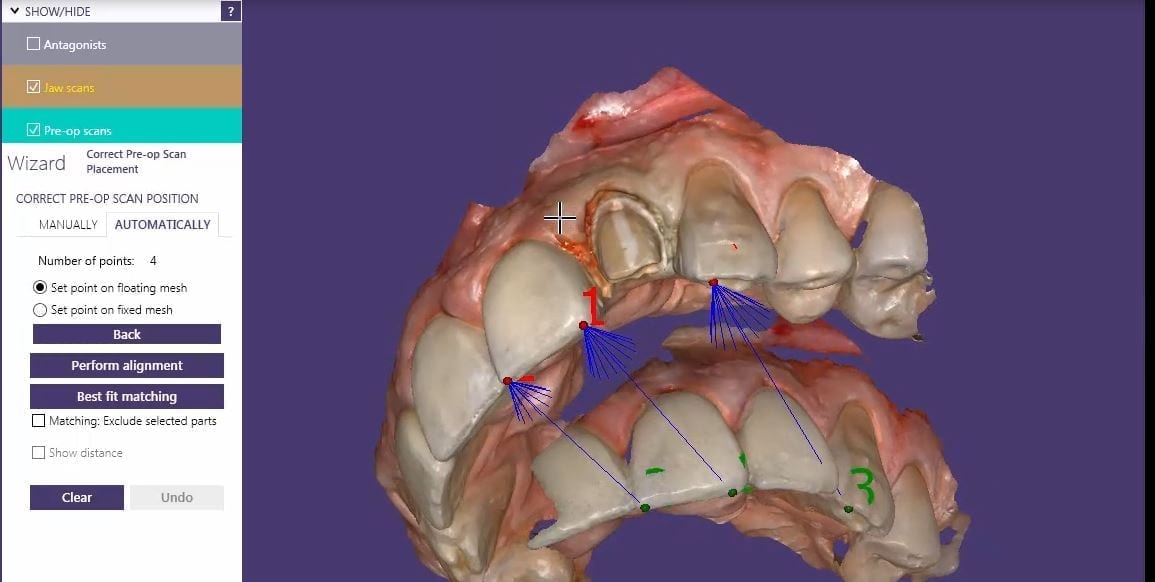

One of the greatest advantages of digital impressions is the ability to copy a pre-existing condition. This has a lot of benefits, one of which is that the patient will […]